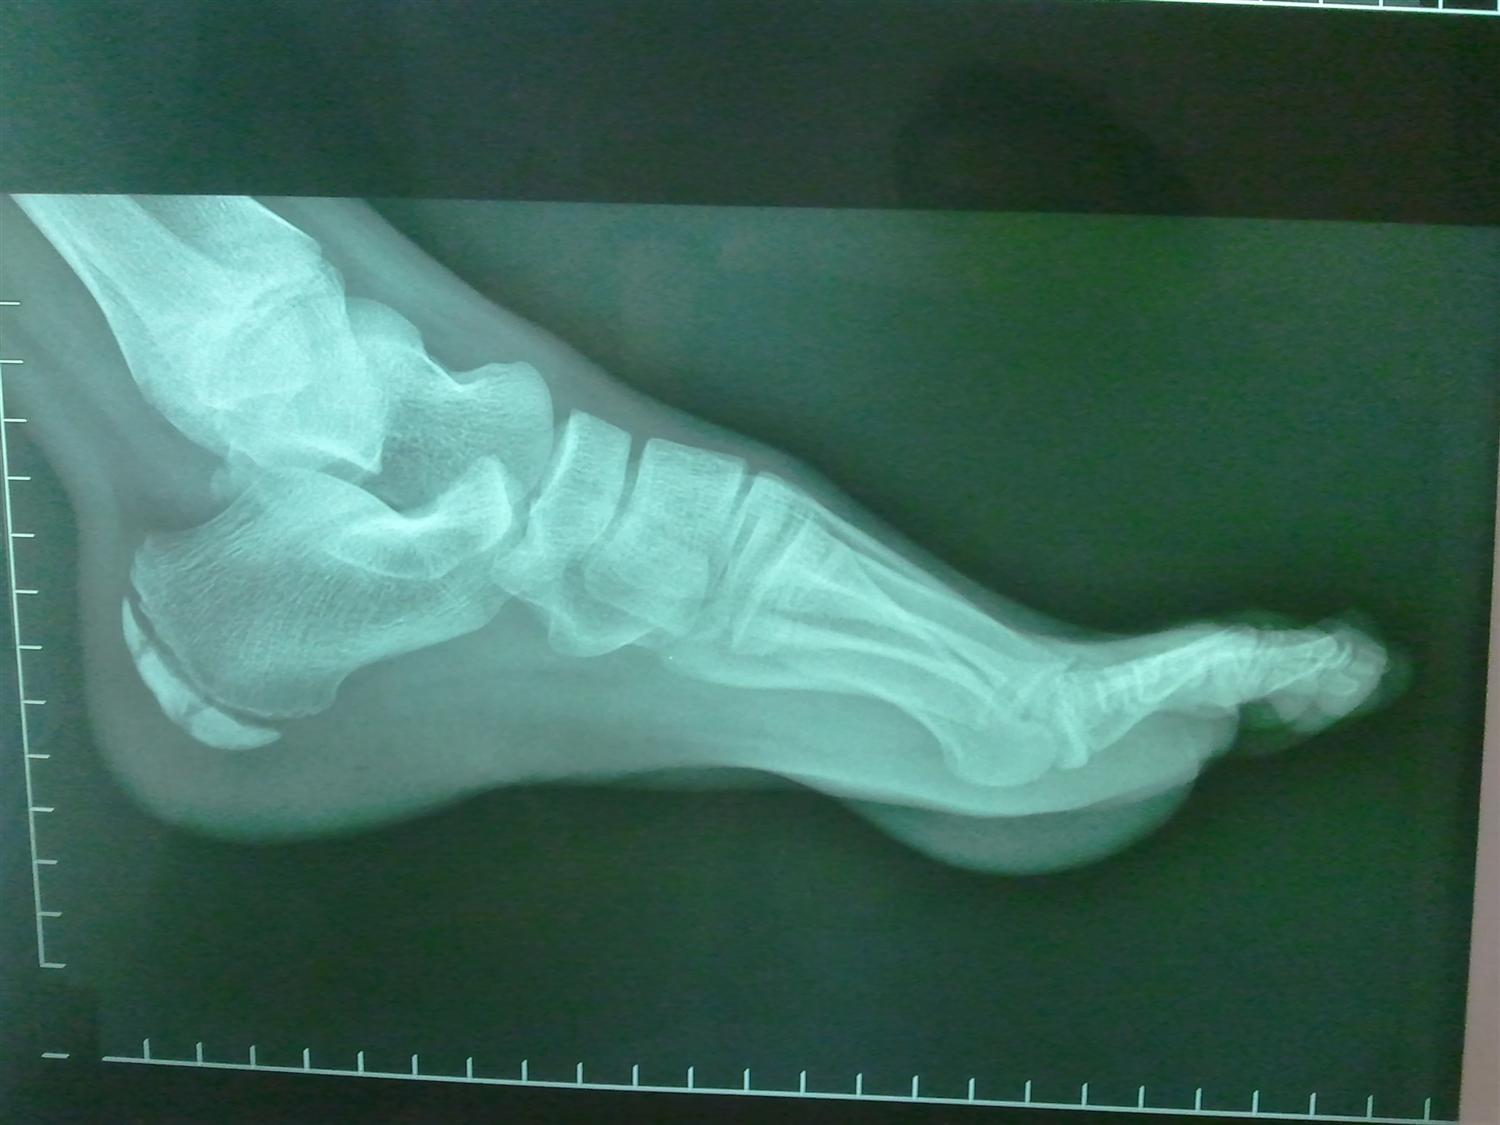

Lower Extremity Os Foot & Ankle Orthobullets Footballers Ankle Orthobullets Ankle sprains are very common twisting injuries to the ankle that are the most common reason for missed athletic participation. Footballer’s ankle, also known as anterior ankle impingement, occurs because bony spurs forms at the front of the ankle joint. Ankle sprains are the most common injuries in sports and recreational activity, accounting for 40% of all athletic injuries,. The. Footballers Ankle Orthobullets.

Osteochondral Lesions of the Talus Foot & Ankle Orthobullets Footballers Ankle Orthobullets The spurs can form at the bottom end of the joint on the. Ankle fractures are very common injuries to the ankle which generally occur due to a twisting mechanism. Footballer’s ankle, also known as anterior ankle impingement, occurs because bony spurs forms at the front of the ankle joint. First termed footballer’s ankle by mcmurray in 1950, ami is. Footballers Ankle Orthobullets.

Footballer's ankle The ankle Biomechanical problems What We Treat Footballers Ankle Orthobullets Ankle sprains are the most common injuries in sports and recreational activity, accounting for 40% of all athletic injuries,. Diagnosis is made with plain. High ankle sprain & syndesmosis injuries are traumatic injuries that affect the distal tibiofibular ligaments and most commonly occur due to sudden external rotation of the ankle. The spurs can form at the bottom end of. Footballers Ankle Orthobullets.

Footballers’ Ankle Footballers Ankle Orthobullets The spurs can form at the bottom end of the joint on the. Footballer’s ankle, also known as anterior ankle impingement, occurs because bony spurs forms at the front of the ankle joint. Ankle sprains are very common twisting injuries to the ankle that are the most common reason for missed athletic participation. He says that prior to symptom development,. Footballers Ankle Orthobullets.